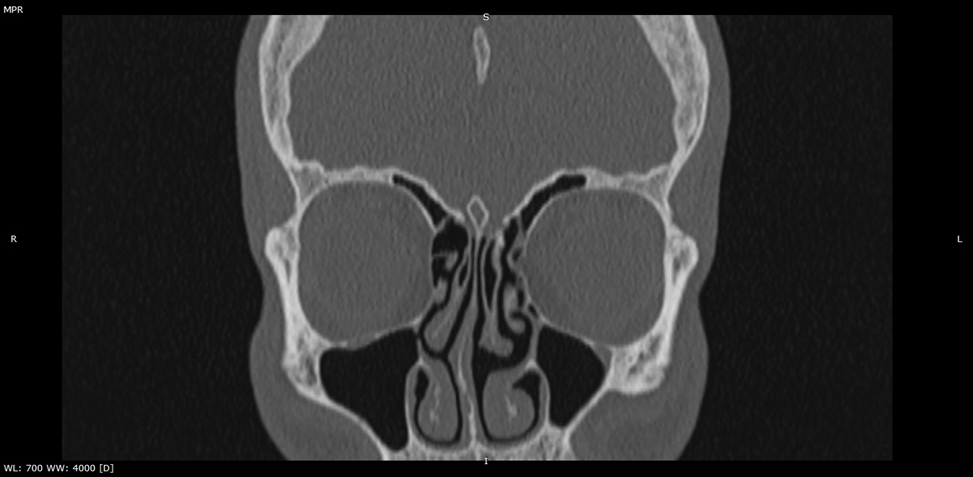

Компьютерная томография околоносовых пазух. Дополнительное соустье левой гайморовой пазухи.